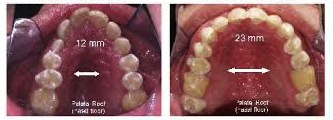

鼻口呼吸上顎寬度與牙弓深度比較

左:口呼吸,上顎成V型發展,前排齒列往前飆,牙弓窄深,鼻腔空間受到壓迫

右:鼻呼吸,上顎成U型發展,前排齒列圓順,牙弓寬敞,鼻腔發育有足夠空間

從上述鼻、口呼吸的對比可知,光是舌頭與空氣的力量,就足以改變整個口腔結構與鼻腔體積空間。鼻呼吸能維持齒列垂直發展,讓上顎牙弓與鼻腔空間寬敞。但口呼吸則會使齒列成V型發展,不僅門牙往前飆,齒列間也會因受到擠壓,致使牙齒參差不齊。